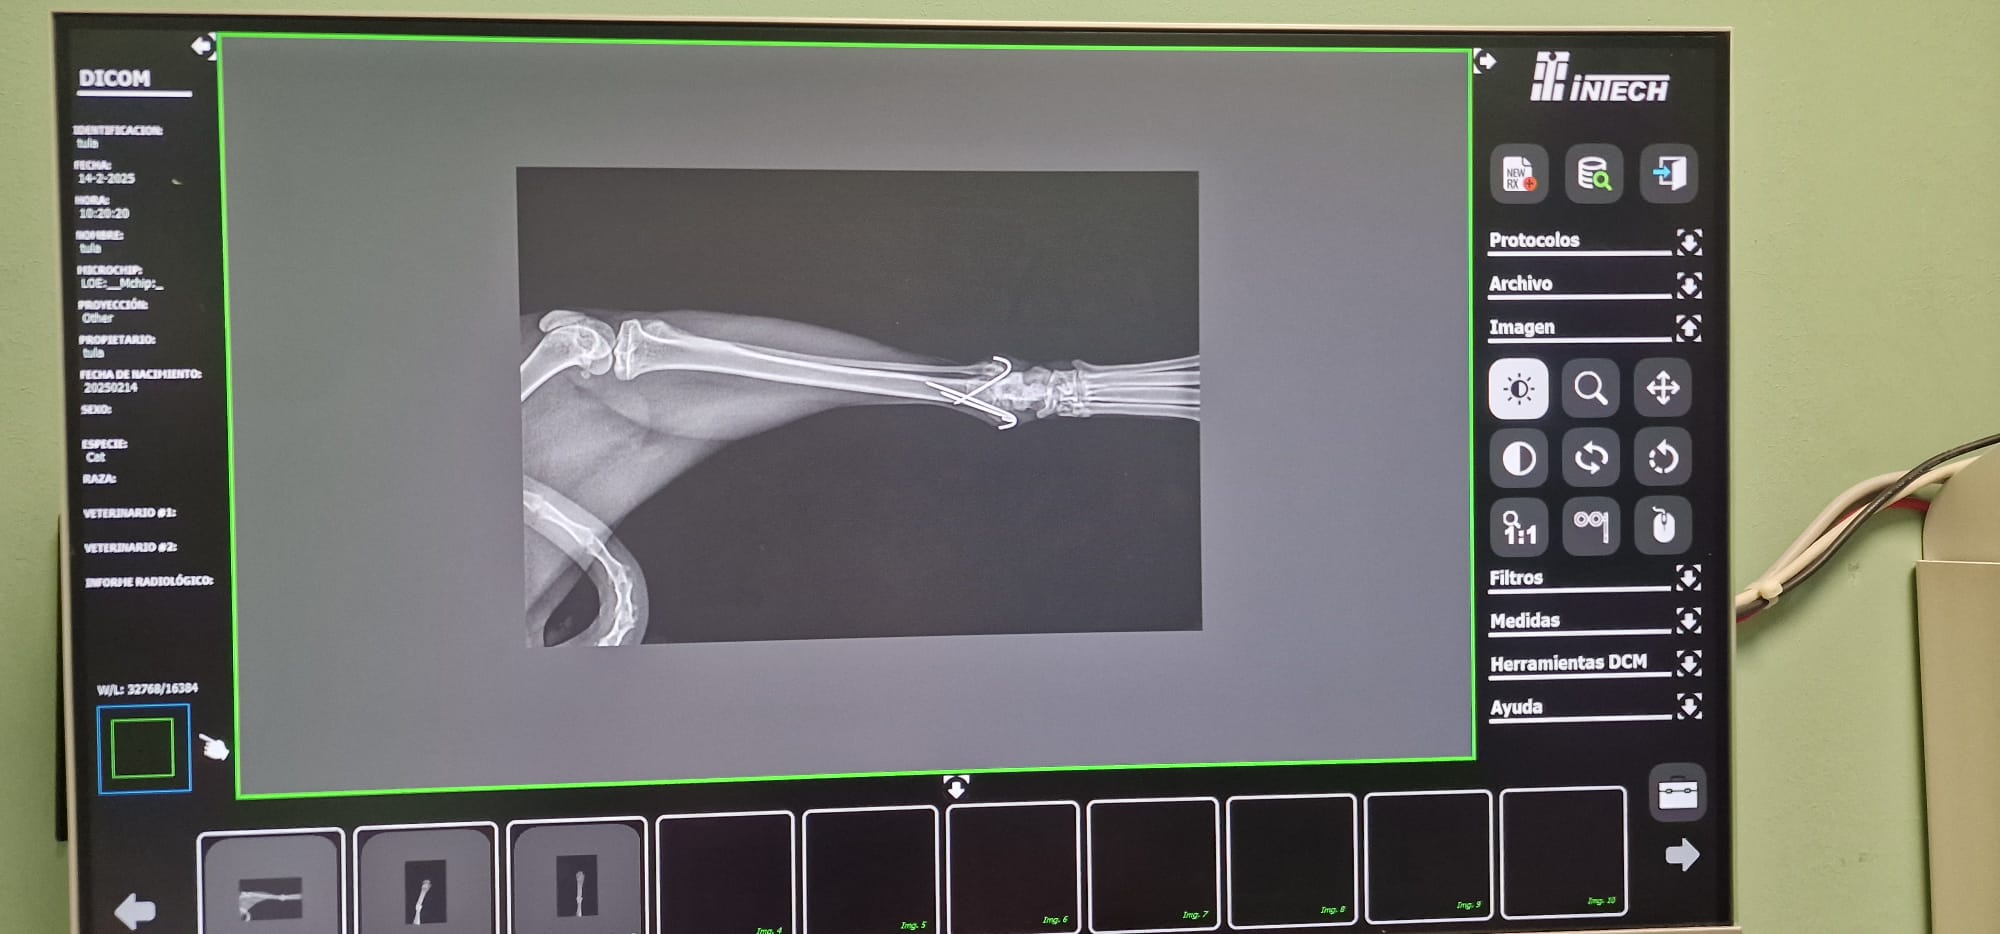

Radiografías = Salud en Imágenes 🐾🩺En Smile Vet, ofrecemos servicios de radiografías para cuidar la salud de tu mascota con precisión y cariño.

• Diagnóstico Rápido: Las radiografías nos permiten detectar problemas (óseos, dentales, respiratorios, cardiacos, etc.) y cuerpos extraños sin procedimientos invasivos. 🐶🐱

• Tecnología Avanzada: Utilizamos equipos modernos para obtener imágenes claras y detalladas, asegurando un diagnóstico eficaz.

• Cuidado Integral: Nuestro equipo interpreta los resultados para ofrecerte el mejor plan de tratamiento, siempre con el bienestar de tu mascota como prioridad. 🐾